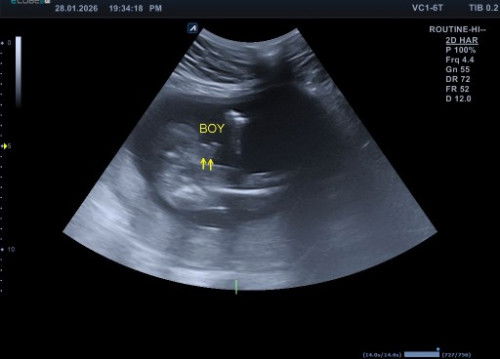

Kira kira kalo hasil usg gini udh pasti jk cowo belum si bun

Soalnya aku mau beli baju baby hihiii #mohonbantujawabbunda #Sharingdong_Bund #firstmom